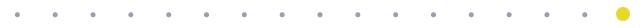

术前CT片